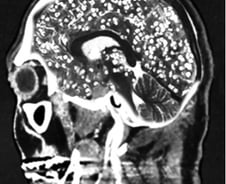

사람의 감정과 행동을 조종하는 기생충이 있다는 사실, 알고 계신가요? 기생충도 사람처럼 중추신경계가 있어 판단력을 갖추고 있는데요. 그중에서도 똑똑한 기생충으로 꼽히는 '톡소포자충'은 사람의 몸속에서 살다가 마지막 단계로 고양이 몸속으로 이동해 교배하는데, 이를 위해 숙주(사람)가 고양이를 좋아하게 만들어 고양이를 키우게 유도한다는 것으로 알려졌습니다. 해외 다수 연구에 따르면 톡소포자충에 감염된 쥐는 고양이 소변 냄새에 대한 공포감이 줄어드는 것으로 확인됐습니다. 또 톡소포자충에 감염된 남성이 그렇지 않은 남성보다 고양이 소변 냄새를 더 좋아했다는 연구 결과도 있습니다. 반면 여성 감염자는 비감염자와 별다른 차이가 없었습니다. '기생충이 몸 안에 들어오면 음식물을 대신 먹어 살이 빠질 것'이란 속설이 있습니다. 지난해 체중 감량에 어려움을 겪던 미국의 20대 여성이 기생충 알이 든 캡슐을 먹고 다이어트하려다 뇌·목·얼굴·혀·간·척추 등에 기생충이 퍼져 끔찍한 부작용에 시달렸다는 사연이 전해졌습니다.